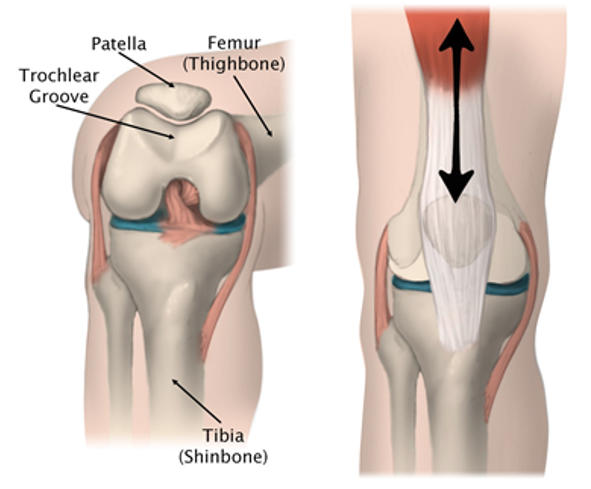

Normal Anatomy Knee

Knee Ligament Injuries ## Footnote * Goal here is to highlight that there are 4 main ligaments of the knee: * (ACL) = * (PCL) = * (MCL) = * (LCL) = * To test them: * _____ → ACL * _______ → PCL * V\_\_\_\_\_→ MCL * V\_\_\_\_\_\_ → LCL

* Goal here is to highlight that there are 4 main ligaments of the knee: * Anterior Cruciate Ligament (ACL) * Posterior Cruciate Ligament (PCL) * Medial Collateral ligament (MCL) * Lateral Collateral ligament (LCL) * To test them: * Anterior → ACL * Posterior → PCL * Varus → MCL * Valgus → LCL